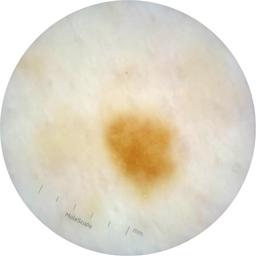

ISIC_9472333

acquisition_day 230

age_approx 65

anatom_site_1 Trunk

anatom_site_2 Anterior trunk

anatom_site_general anterior torso

diagnosis_1 Benign

diagnosis_confirm_type single image expert consensus

family_hx_mm True

fitzpatrick_skin_type I

image_manipulation instrument only

image_type dermoscopic

personal_hx_mm True

sex female